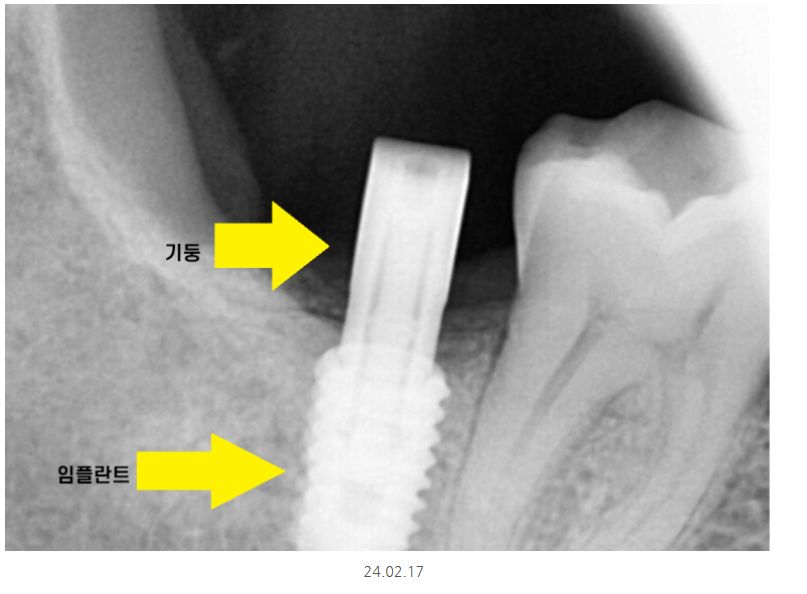

하남시청치과 임플란트 그 결과는,,?

짜잔~~

원하는 위치에 정확히 들어갔습니다.

3개월 뒤에 뼈와 충분히 붙어서

기둥을 올리고 보철을 올려드렸습니다.